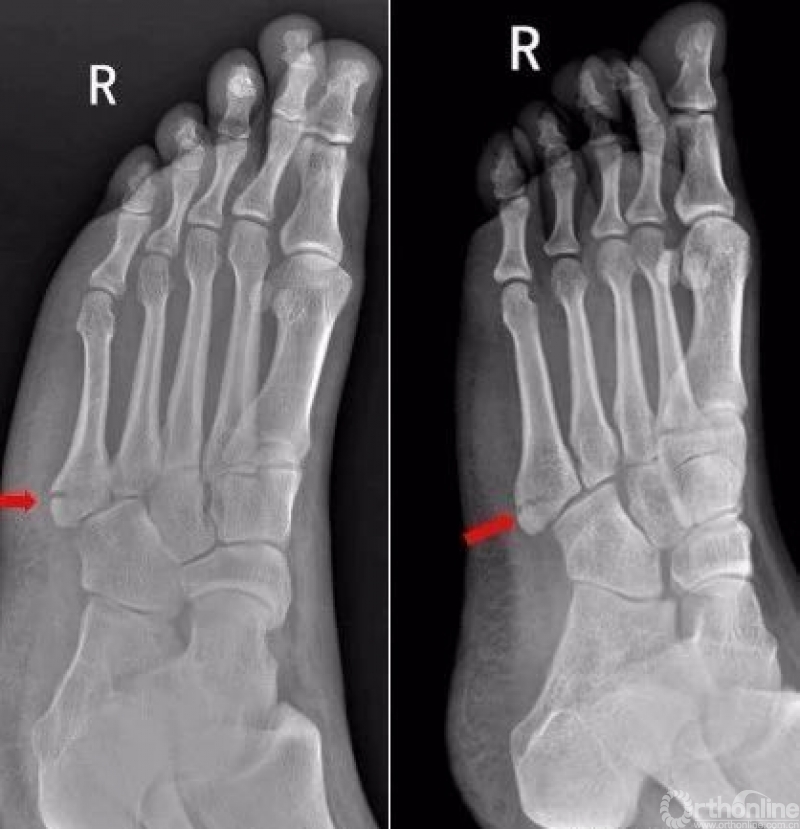

右足第5跖骨基底部见骨折线,断处稍分离移位。右足第5跖骨基底部骨折

Warmreminder: 儿童时期足第5跖骨处有骨骺存在,骨骺线易与骨折线混淆,小妙招给你,骨骺线的长轴一般是与第5跖骨长轴平行,而第5跖骨多是横行骨折,换言之骨折线与第五跖骨长轴垂直。